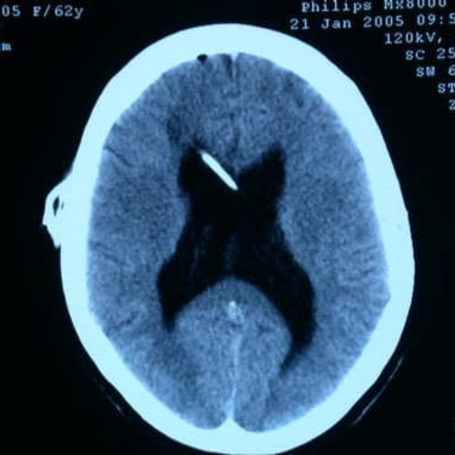

Hidrocefalia comunicante

Diagnóstico: Se realiza mediante evaluación clínica y estudios de imagen como tomografía computarizada (TAC) o resonancia magnética (RM), que muestran la dilatación ventricular. En algunos casos, se requieren estudios adicionales para identificar la causa subyacente.